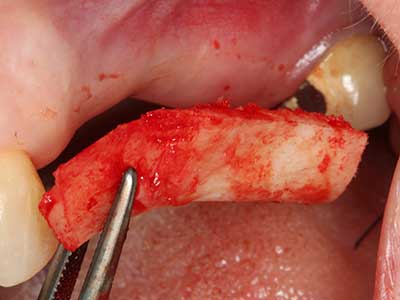

Фиг. 18: Препарация на кортикално покритие с пиезо накрайник за кост (Piezomed, W&H).

Фиг. 19: Хирургичното поле след невролиза и отстраняване на остеотом.